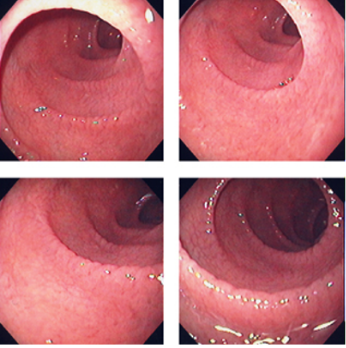

What is seen here?

Dilated pancreatic duct with strictures and abnormal appearance due to CHRONIC PANCREATITIS